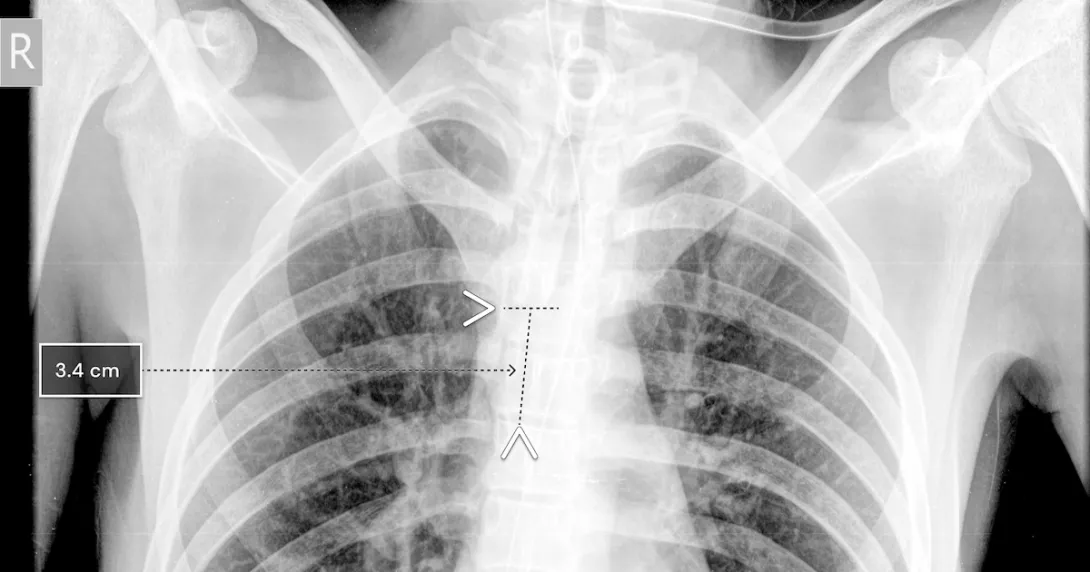

Using chest x-rays, the qXR-BT algorithm can analyze the position of the breathing tube. It automates measurement and can report accuracy to the clinician, who can then decide if the tube needs to be re-placed.